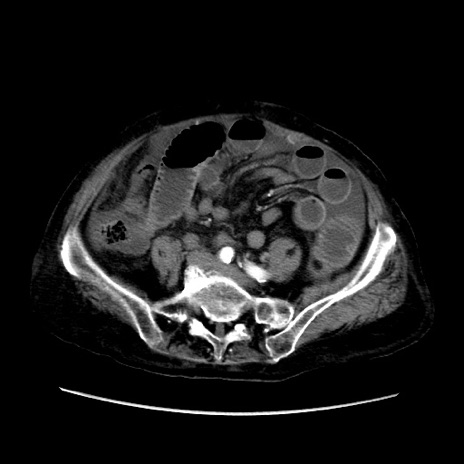

矢状断像

【症例】80歳代 女性

【主訴】腹部膨満感

【現病歴】他院にて肝硬変にてフォロー中。1週間前から便秘、腹部膨満感、臍部腫瘤あり受診となる。

【既往歴】肝硬変

【身体所見】腹部膨隆あり、皮膚変化なし、疼痛なし。

【データ】WBC 4600、CRP 0.25